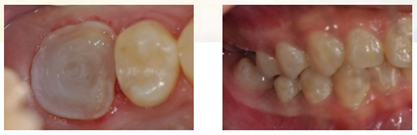

1、局麻下,Er-YAG激光切除增生牙龈

2、使用组织排开橡皮障夹(#B-1)上橡皮障,障布边缘翻转,隔离牙龈,封闭患牙。

3、去净腐质后,剩余健康牙体组织位于龈下,考虑行龈壁提升,因需使用成型片,拆除橡皮障。

4、使用成型片隔离牙龈,保证边缘密合不渗漏,SDR树脂龈壁提升。

5、进行正式根管治疗前,仍需对近中邻面龋坏牙体组织进行处理。

6、上橡皮障,去除近中龋坏组织,SDR树脂制作近中邻面假壁。

7、初步恢复牙体完整性后上橡皮障,开髓,3% NaClO冲洗,揭除髓顶,修整开髓洞形,去除髓腔牙髓组织。

8、定位根管口后,8#K锉结合根管冠方预敞,逐步探查,四根管通畅。因操作时间过长,未作根管预备,氢氧化钙糊剂暂封根管一周,玻璃离子暂封。